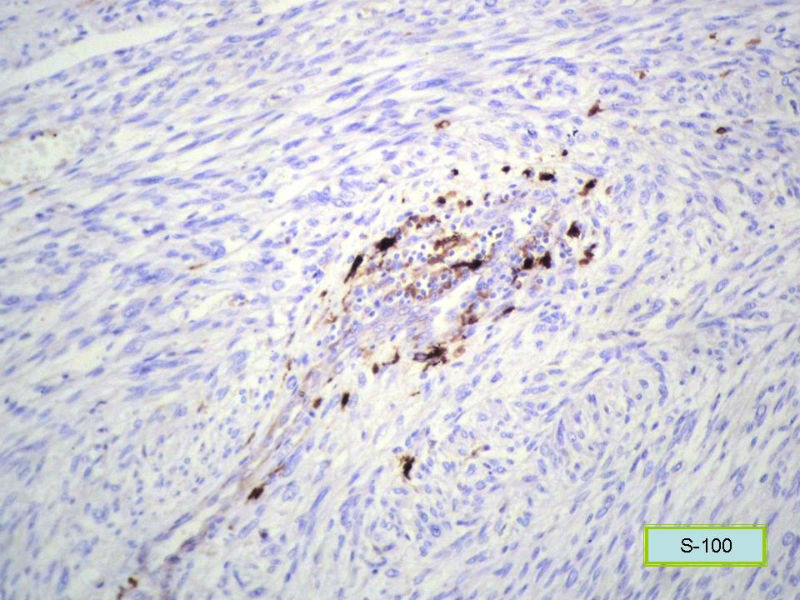

女,71岁,胸闷2月余,CT提示纵膈占位。手术见左肺与胸膜之间有一肿块,与周围粘连,手术切除。肉眼,肿块7X5X3厘米,边界较清楚,切面灰白灰红,质韧。

镜检:核分裂5</10HP

此例我们诊断为平滑肌肉瘤,因为很少见,请各位老师讨论!

形态学和免疫组化标记符合平滑肌肉瘤,但要标记Myogenin等鉴别横纹肌肉瘤,标记D2-40、Calretinin等鉴别肉瘤样间皮瘤。